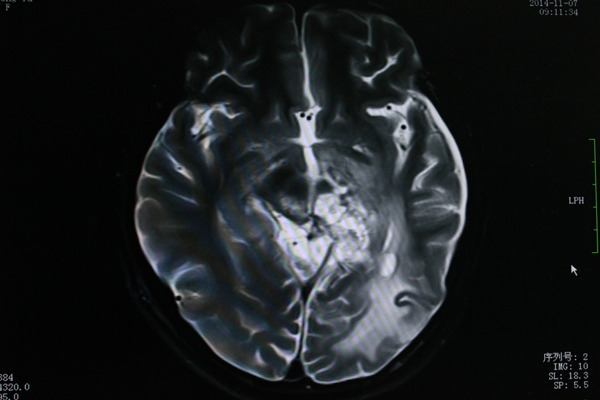

8岁的文文今年上小学二年级了,谁也想不到活泼好动的他,在三年前被检查出患有脑胶质瘤。日前,文文在父母的带领下来院复查。磁共振结果显示胶...